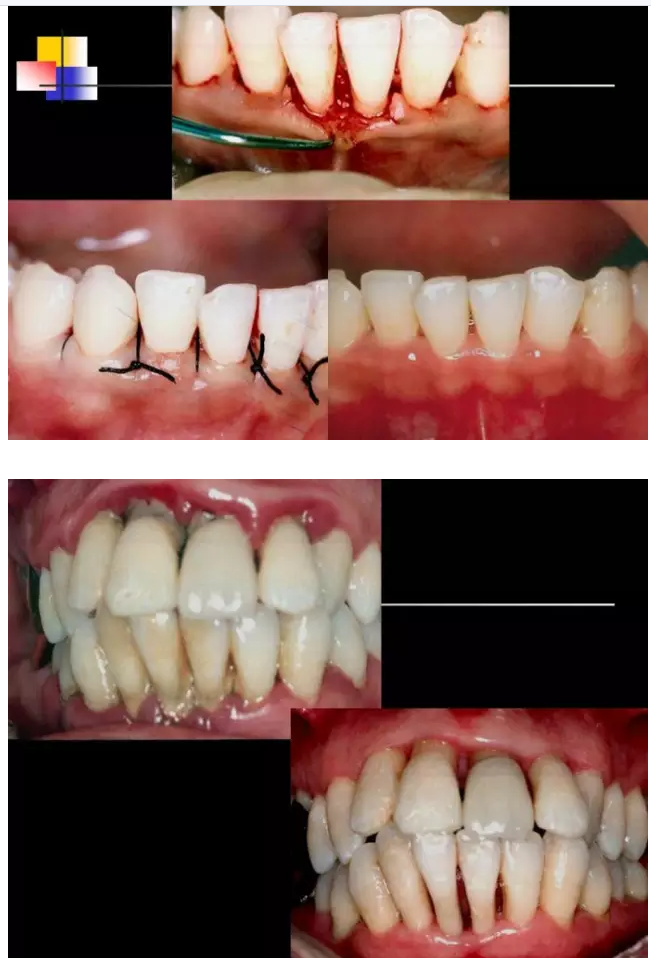

相關(guān)牙周防治